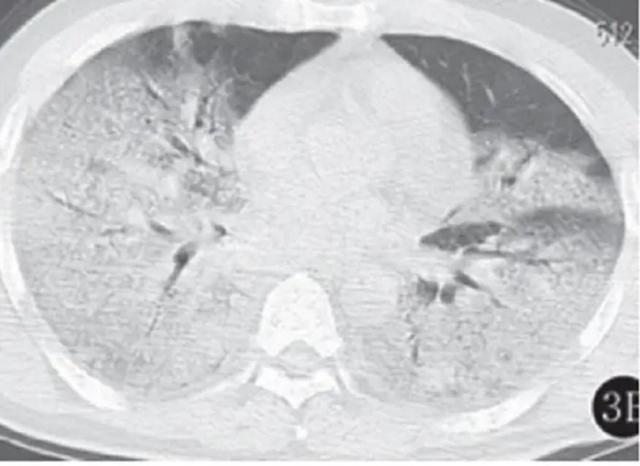

3、早期表现早期肺部CT以单发外周肺野磨玻璃影为主,表现为局部肺组织密度轻度增高,但仍可见血管及支气管纹理。此阶段磨玻璃影反映肺泡内渗出性改变,与病毒主要侵犯肺外周组织的特点相关。对于有新冠病毒接触史且出现呼吸道症状者,早期发现磨玻璃影需高度警惕新冠感染可能。

4、新冠患者出现“大白肺”是影像学上的一种表现,指的是双肺大部分失去了作用,在CT上呈现为白色。这通常意味着患者的病情已经相当严重,因为肺组织是用来呼吸的,当肺泡内充满液体或细胞成分时,空气就无法被吸入,导致患者产生窒息感,无法缓解缺氧症状。

5、新冠感染患者的CT影像表现主要包括以下方面: 肺部磨玻璃影和实变影这是新冠感染最常见的CT表现。磨玻璃影反映肺部炎症,表现为局部肺组织密度轻度增高,呈云雾状;实变影则提示肺泡内充满炎症细胞和渗出物,导致肺组织密度显著增高,类似肺炎表现。二者常同时出现,提示病变进展。

“大白肺”通常出现在危重症患者中,是肺部炎症非常严重的表现。当肺部出现“大白肺”时,基本上失去了气体交换的能力,患者会出现明显的缺氧、呼吸费力等症状,末梢血氧饱和度也会下降。对于这类患者,通常需要呼吸机辅助呼吸,甚至需要ECMO体外生命支持来维持生命。

新冠患者出现“大白肺”并不意味着生命绝对倒计时,有效治疗方法确实存在。新冠患者出现“大白肺”是影像学上的一种表现,指的是双肺大部分失去了作用,在CT上呈现为白色。